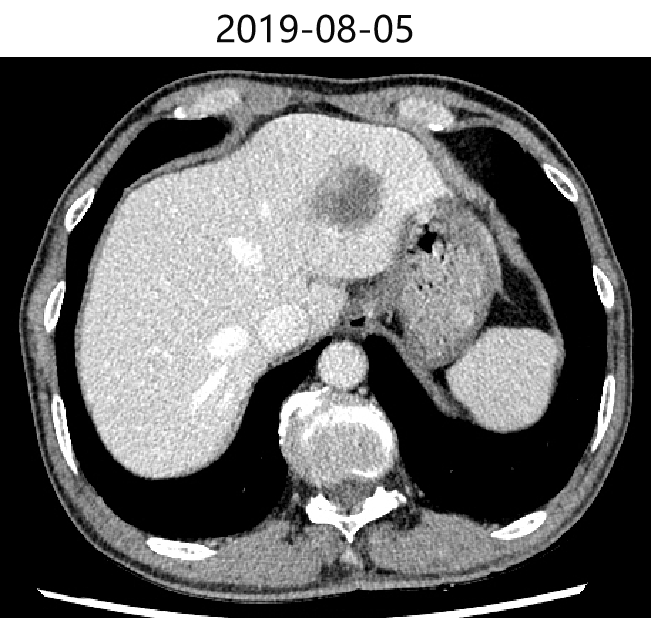

2019-08-05 胸腹部增强CT提示:双肺多发结节影,部分考虑转移可能,建议抗炎治疗后复查;双上肺肺气肿,多发肺大疱;脊柱胸段S形侧弯;胃术后改变;肝脏多发囊肿;肝左叶占位,考虑转移;胆囊结石;左肾小囊肿;前列腺钙化;直肠管壁局部增厚,考虑直肠癌可能,建议结合肠镜活检。

肝:肝左叶占位,考虑转移。